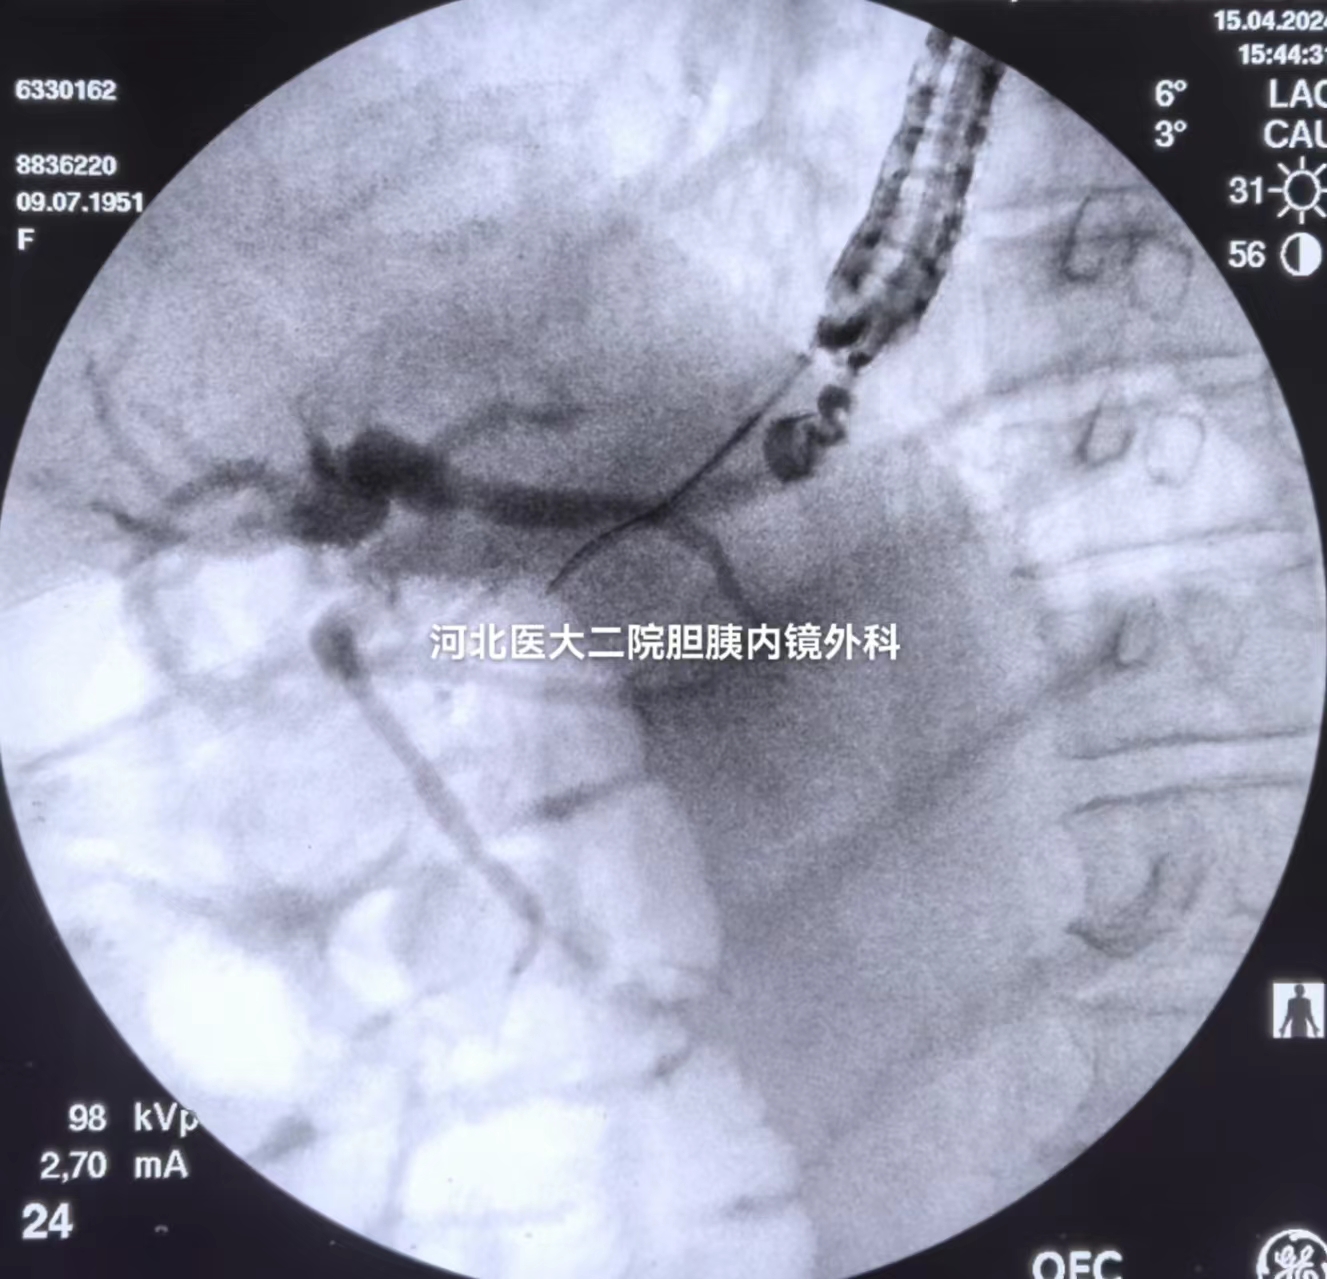

穿刺

造影